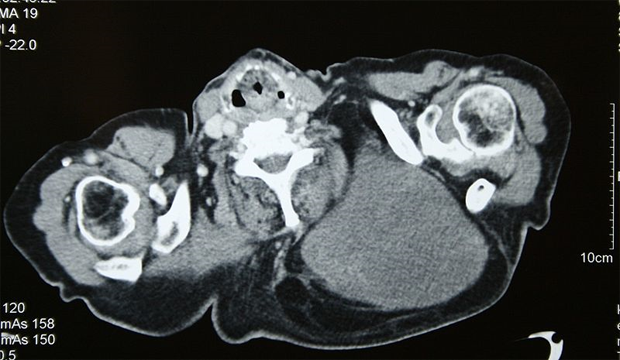

Chest CT of liposarcoma; source: Kuebi, Wikimedia Commons